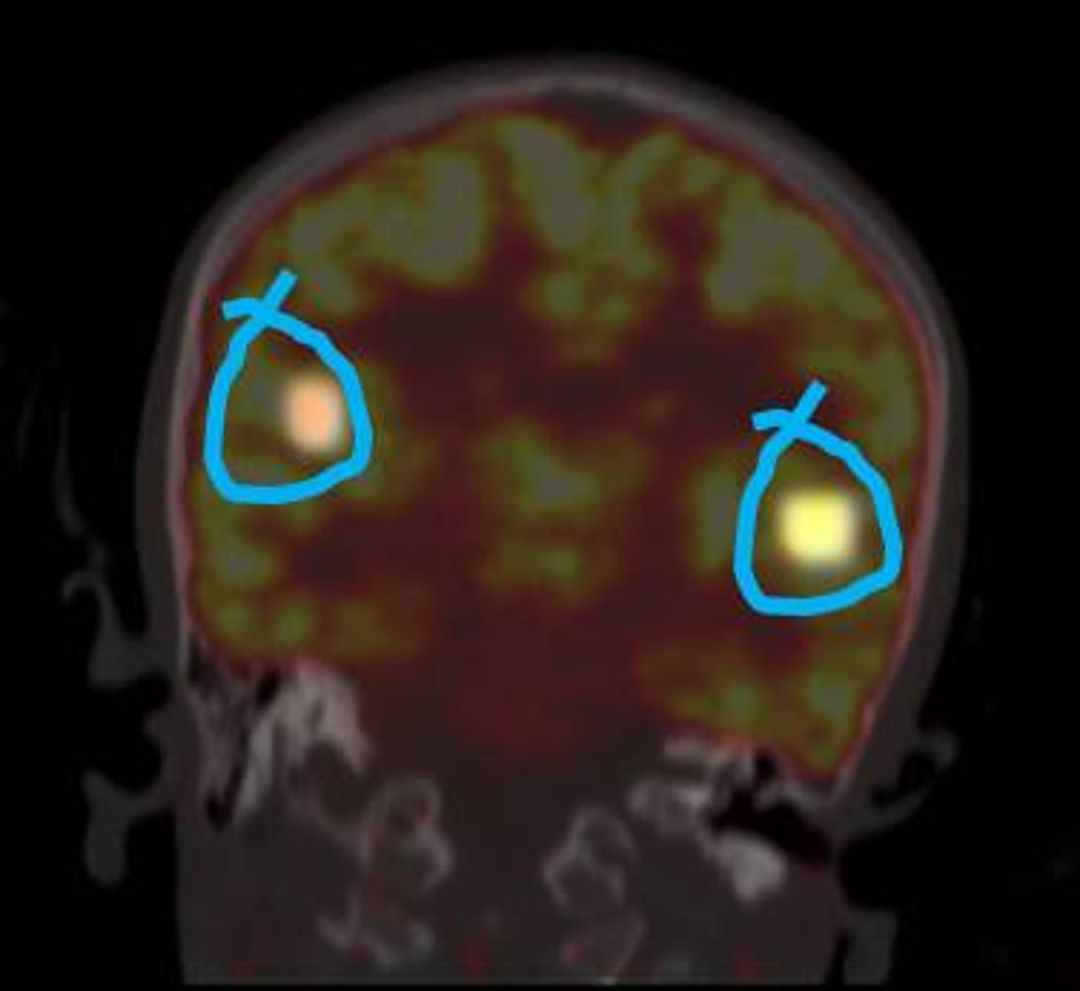

On the contrary avid uptake was noted in lateral cingulate gyrus, mid pons and periaqueductal grey [PAG] in cases of underactive detrusor (Figures 2 a, b, c and d). Again these findings were correlated with the neuroanatomical and physiological regions of the brain it was noted that hyper metabolism in these areas has been recorded during strong urge or the act of micturition (7, 10, 11, and 14).

In cases overactive bladder TcPTNS decreased the activity in the cerebellum, midbrain and adjacent midline thalamus and limbic cortical areas, i.e. the cingulate gyrus, ventromedial orbitofrontal gyrus and prefrontal cortex. These are the areas involved in the sense of bladder filling. While, FDG uptake was more avid in these areas before the start of TcPTNS. On contrary the avid uptake was noted in hypothalamus and prefrontal area in cases of underactive detrusor. These are the areas involved sensorimotor learning and the initiation of voiding.